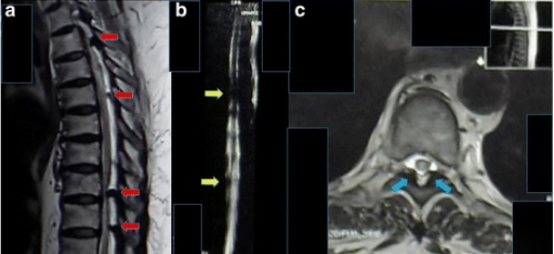

進(jìn)行了胸部X光檢查,結(jié)果正常(見圖1)。T1加強(qiáng)磁共振成像顯示,Th8和Th9椎體后方硬膜內(nèi)位置有一個規(guī)律性的低強(qiáng)度病變,主要位于左側(cè)。該病變壓迫了脊髓向左。在T2加強(qiáng)磁共振成像中,病變相對于正常脊髓具有等強(qiáng)度(圖2)。

1 胸腔區(qū)域、前后側(cè)和側(cè)面的普通X光片。a 前后視角顯示脊柱畸形及胸椎周圍的腫塊沉積過程(紅色箭頭)。b 側(cè)面圖顯示脊柱管某一水平處有退行性腫瘤沉積(黃色箭頭))

2 胸腔磁共振成像的矢狀面和軸向視圖,采用T1加強(qiáng)和T2加強(qiáng)圖像。a .T2加強(qiáng)磁共振成像的矢狀切片顯示,T3、T5、T8和T9等水平處多處脊髓受壓(紅色箭頭)。b . 磁共振成像-脊髓造影顯示T5和T9(黃色箭頭)水平處脊髓壓迫。c . T5椎骨水平的軸向視圖顯示左后部和右側(cè)的低強(qiáng)度腫塊(藍(lán)色箭頭)。